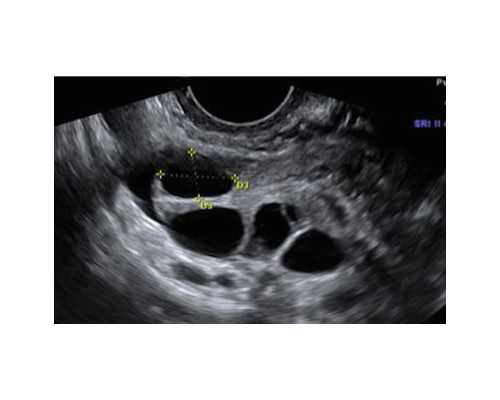

1、在孕周期满5周以上时,经过B超检测出有胎心,并且显示有卵黄囊时便可以进行检测。

1、孕妈妈怀孕满6周,B超确认胚芽长度达到5毫米。

1.必须胎龄满6周或以上,并且有注明已孕满6周或以上字样或者胚芽直径在10MM或以上的B超单。